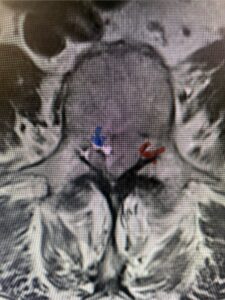

The next patient is a 56-year-old morbidly obese female who had progressive leg pain and weakness. She was over 320 lbs and did not have diabetes either. On MRI she had a massive disc herniation spanning the L3-4 and L-4 interspaces, centered behind the L4 vertebral body (Fig 3A and B). She also had an L4-5 spondylolisthesis. There were opinions that the disc emanated from the L3-4 disc space, but because of spondylolisthesis and on careful inspection of the MRI, there was a high chance the disc herniation had instead emanated from L4-5 (Fig 4). She had conservative treatment including epidurals but had worsening strength and numbness. She was scheduled electively for surgery, but then fell, and broke her ankle. She could not walk, particularly due to the pain down her leg. She was taken to the operating room urgently after she was cleared medically. She had no issues cardiologically and was taken to the operating room. The patient underwent a laminectomy that extended above the L3-4 disc space to below the L4-5 disc space. We encountered mainly centered on the left at the level of the L4 vertebral body and massive disc herniation that created a huge cavity in the lumbar canal. It was covered in an interesting thin membrane that we dissected off the disc herniation (Fig 5). Postoperatively the patient did experience significant relief of pain, but some improvement of strength. In combination with the ankle fracture and the extent of preoperative weakness, the patient required extensive rehab. The patient also developed a seroma and some wound drainage issues that were treated locally.

Fig. 3b: Axial T2-weighted lumbar MRI demonstrating severe compression of the thecal sac (blue arrow) by the large left sided disc herniation (red arrow) taking up most of the left side of the spinal canal (red arrow)